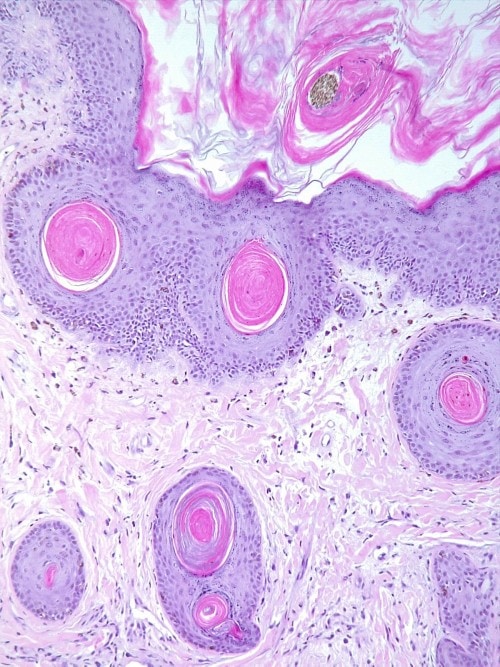

L’hypothèse d’une dermatomyosite familiale canine, maladie pour laquelle le Beauceron est prédisposé, reste la plus probable et des biopsies cutanées pour analyse histopathologique sont réalisées. Cette dernière montre une dermatite d’interface pauvre en cellules caractérisée par une mucinose dermique, une atrophie des annexes, une vasculopathie, une dégénérescence musculaire mais également par une hyperkératose épidermique et folliculaire marquée. L’aspect histopathologique est compatible avec l’hypothèse de dermatomyosite familiale canine et évoque la dermatomyosite de type Wong décrite chez l’humain (cf. photos 7 à 9).

Photos 7-9 : aspect histopathologique des lésions : notez l’acanthose, l’hyperkératose orthokératosique modérée à très marquée épidermique et folliculaire et l’atrophie annexielle (photos 7 et 8) ainsi que la présence d’images de vacuolisation et d’apoptose de la couche basale de l’épiderme associées à une incontinence pigmentaire (dermatite d’interface pauvre en cellules (photo 9).